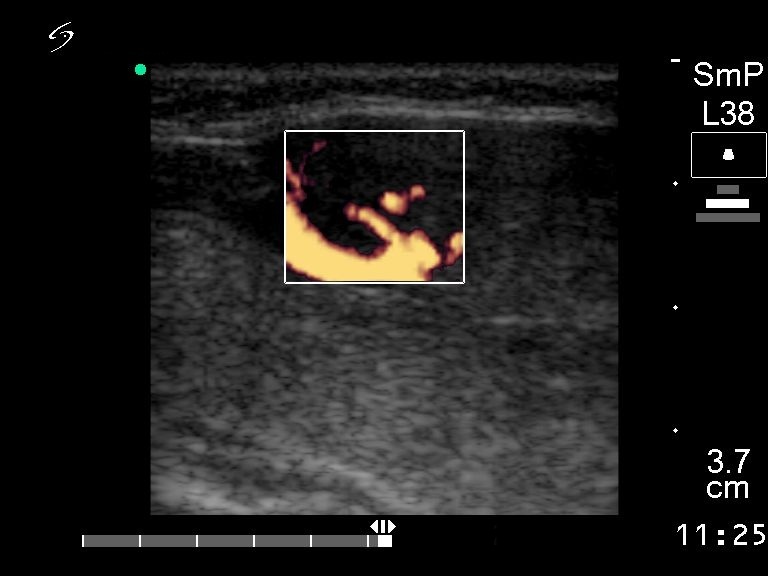

Halo sign and vascular pattern of nodules - case 304 (ultrasonographic picture 6)

Lower part of the right lobe, longitudinal scan, power Doppler method. There is a large vessel on the dorsal surface of the mass. It corresponds to perinodular flow. The intranodular vascularization is also increased. Taken the gray-scale and power Doppler images together into account, one can conclude that this mass is of thyroid origin. The perinodular flow excludes the possibility that this lesion is a lymph node.